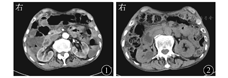

患者男,86岁,因恶心、呕吐伴消瘦半年余于2014年7月21日入院。入院前半年无明显诱因下出现间歇性恶心、呕吐,每5~6 d发作1次,每次持续1 d,呕吐物为胃内容物及黄绿色胆汁,呕吐后恢复正常,无腹痛、纳差,半年内体质量减轻15 kg。既往无高血压、糖尿病、心血管疾病史。入院体格检查:消瘦貌,皮肤巩膜无黄染,血压120/70 mmHg(1 mmHg=0.133 kPa),心率72次/min,律齐,两肺呼吸音粗,未及啰音,腹平软,无压痛,肝脾肋下未及,双下肢无水肿。2014年5月25日外院上腹部增强CT示:十二指肠远端近空肠处肠壁局部增厚伴周围淋巴结增大,考虑肿瘤可能大,十二指肠水平段局部受压,十二指肠淤积?2014年6月23日复查上腹部增强CT,提示肝脏多发小低密度灶,肝门部胆管扩张,胰腺萎缩(图1)。小肠CT未见明显异常(图2)。胃镜示浅表性胃炎。

入院后完善各项实验室检查。血常规:Hb 100 g/L,余正常;尿、粪常规、凝血功能正常。肝功能:总胆汁酸13.8 μmol/L,总蛋白53 g/L,白蛋白32 g/L,球蛋白21 g/L,前白蛋白215 mg/L,碱性磷酸酶45 U/L,γ–谷氨酰转酞酶20 U/L,葡萄糖4.9 mmol/L。肾功能:尿素7.9 mmol/L,肌酐71 μmol/L,尿酸78 μmol/L。电解质:钾、钠、氯化物、钙、磷、镁、铁均正常。血脂:总胆固醇2.52 mmol/L,三酰甘油0.32 mmol/L,高密度脂蛋白0.87 mmol/L,低密度脂蛋白1.47 mmol/L。血清肝炎标志物:抗–HBs 35.64 U/L,余均阴性。肿瘤标志物:AFP、CEA、CA19–9、糖类抗原50、糖类抗原72–4均正常。腹部X线平片(立卧位)未见明显异常。超声检查:肝右叶高回声结节,考虑血管瘤可能,肝质不均,胆囊胆固醇结晶,胰体、脾未见明显异常,门静脉系统、肝静脉系统、脾静脉系统彩色多普勒超声参数未见明显异常,中上腹腹主动脉旁未见明显异常肿大淋巴结。十二指肠低张钡剂造影:胃、十二指肠及部分小肠内见造影剂影;十二指肠降部扩张,造影剂潴留。钡剂通过十二指肠水平部缓慢,十二指肠于空肠交界处黏膜紊乱,1 h后腹部X线平片检查示十二指肠降部扩张,造影剂潴留,考虑十二指肠水平部肠腔狭窄(图3)。经口小肠镜(图4):十二指肠水平部占位(增殖性病灶,绕肠一周,肠腔狭窄)。遂转至外科进行手术治疗,术中见十二指肠、横结肠肝曲与胆囊粘连,肿瘤位于距屈氏韧带约4 cm处,侵及肠腔一周,累及浆膜外。切除标本示病灶为溃疡型肿块,大小为5.0 cm×1.5 cm×0.5 cm,切面灰白、质硬,累及肠管一周,浸润管壁全层。肠系膜少量脂肪组织中找到结节样组织2枚,最大径为0.5~1.2 cm。组织病理学诊断:腺癌Ⅱ~Ⅲ级,浸润至浆膜外,侵犯神经;肠系膜结节样组织中1枚为淋巴结,见癌转移,另1枚为癌结节(图5)。术后诊断为十二指肠腺癌。术后2周出院,出院后随访2个月,患者进食可,无腹胀等不适。